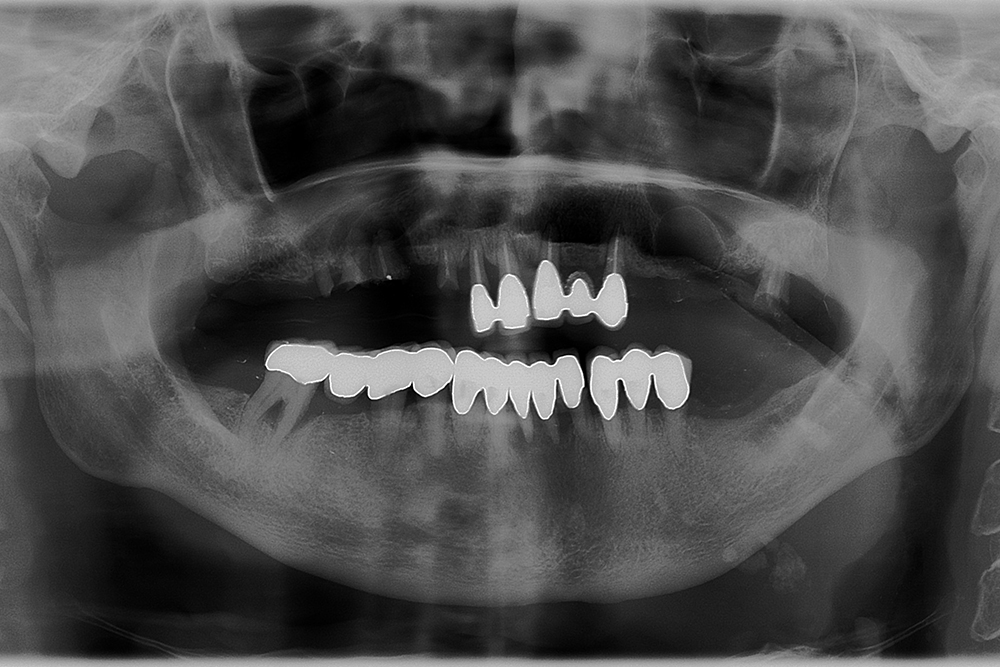

Ripristino dell’arcata superiore su overdenture su barra